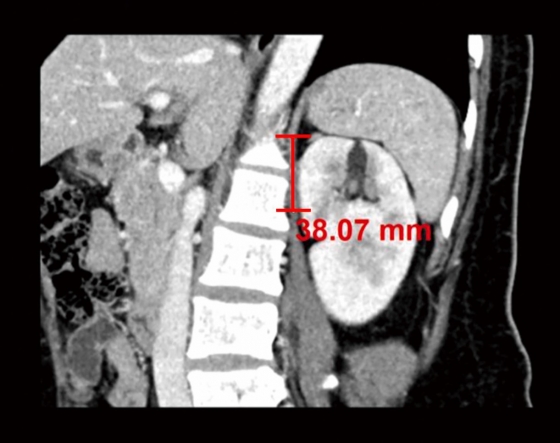

ÀÌ ¿¬±¸¿¡¼­ ´Ùº¯·® ·ÎÁö½ºÆ½ ȸ±ÍºÐ¼®*À» ÅëÇØ ¼ö¼ú½Ã°£°ú ȯÀÚµéÀÇ ¡ã¼ºº° ¡ã¿¬·É ¡ã±âÀúÁúȯ ¡ãÁ¾¾çÀÇ Æ¯¼º µîÀ» ºÐ¼®ÇØ ¼ö¼ú½Ã°£ ¿¬Àå ¿¹ÃøÀÎÀÚµéÀ» È®ÀÎÇÑ °á°ú ºÎ½ÅÁ¾¾ç ÇϺο¡¼­ ½ÅÀå »óºÎ±îÁöÀÇ ¼öÁ÷ °Å¸®°¡ ¼ö¼ú½Ã°£À» ¿¬Àå½ÃŰ´Â ÁÖ¿ä ¿¹ÃøÀÎÀÚÀÎ °ÍÀ¸·Î ¹àÇôÁ³´Ù.

¡ã ºÎ½ÅÁ¾¾ç ÇϺο¡¼­ ½ÅÀå »óºÎ±îÁöÀÇ ¼öÁ÷ °Å¸®